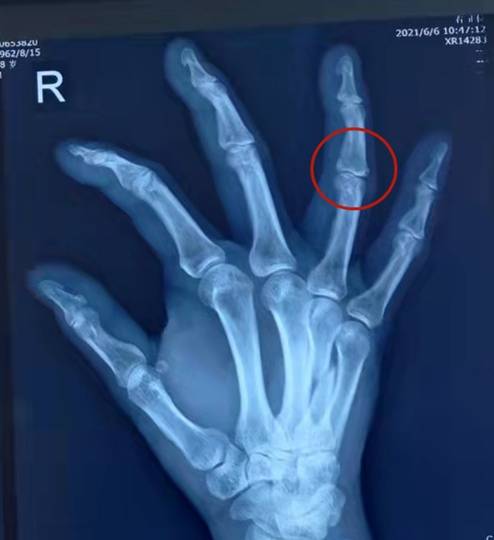

经朋友介绍来到梁氏骨科后 , 拍片显示王先生右手第四掌骨骨折 , 手指生疼 , 干架时的气势瞬间完败 。 问及受伤原因时 , 王先生吞吞吐吐地不想说实话 。 已经心中有数的梁雪梅院长解释说:“看您这骨折的片子 , 从受伤机理上就能诊断您是捶伤的 , 全面掌握病情 , 才能更好地给您复位 。 ”

整复前

整复后

梁雪梅院长为其实施手法整复后 , 王先生小心翼翼地抱着、心生爱怜地看着被固定包扎的手指 。 一声长叹:“这回可是真挨'整'了 , 今后再也不借酒消愁!好在是用手法正骨 , 要是为此做手术 , 我得后悔死 。。。。。。 ”